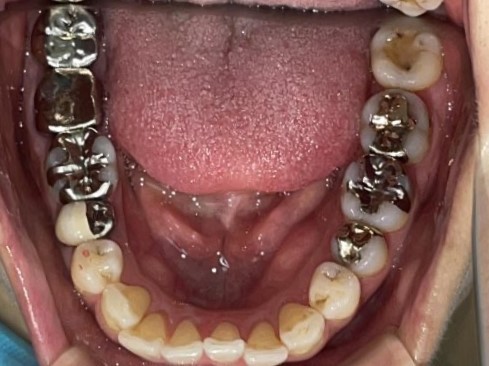

Before

After

矯正の種類 / invisalign GO

年齢・性別 / 30代女性

主訴  /  叢生、交叉咬合

治療期間 / 17ヶ月

費用 / 簡易検査 5,000円(税別) 精密検査 30,000円(税別)

両顎マウスピース 450,000円(税別) 両顎リテイナー料 60,000円(税別)

※マウスピース交換時別途調節料5,000円(税別)

副作用 / 口内炎・歯の移動に伴う痛み・知覚過敏 ※数日で収まる場合が多いです

リスク / 後戻り防止の為、夜のみマウスピースで保定を指示